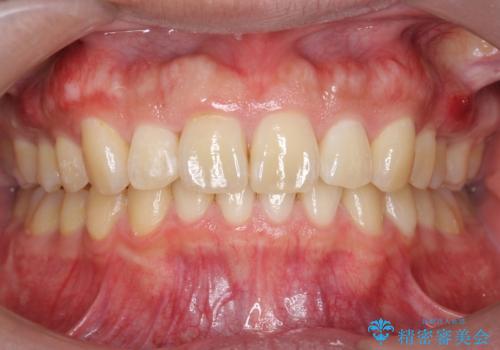

[ インビザライン ]飛び出た前歯を抜かずに矯正治療

担当医 大元洋佑